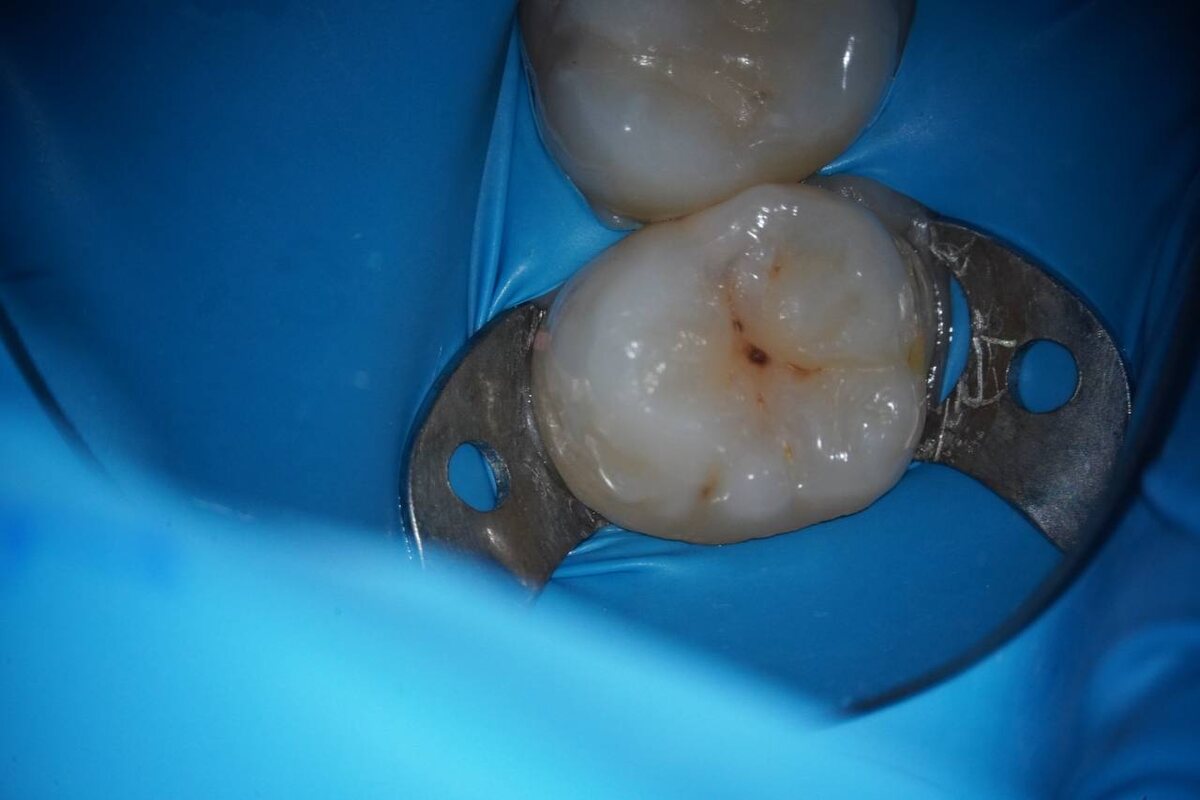

🩸 Контактный кариес

Тот самый, который прячется между зубами, как шпион в кино, и говорит: «Ну ты же меня не видишь? Значит, всё ок!»

А потом — бах! — и ты слышишь: «Ой, а тут уже дырочка… и глубокая…»

Он любит узкие промежутки, любит, когда щётка не достаёт, а нить — в лучшем случае лежит в ванной как декор.

Он не кричит, не свербит, он подкрадывается.

И только рентген скажет: «Да, брат, ты уже в зоне поражения».